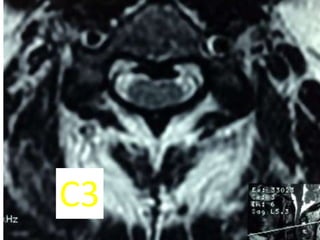

C3

C3C4

C4C5

C5C6

C6C7

C7T1